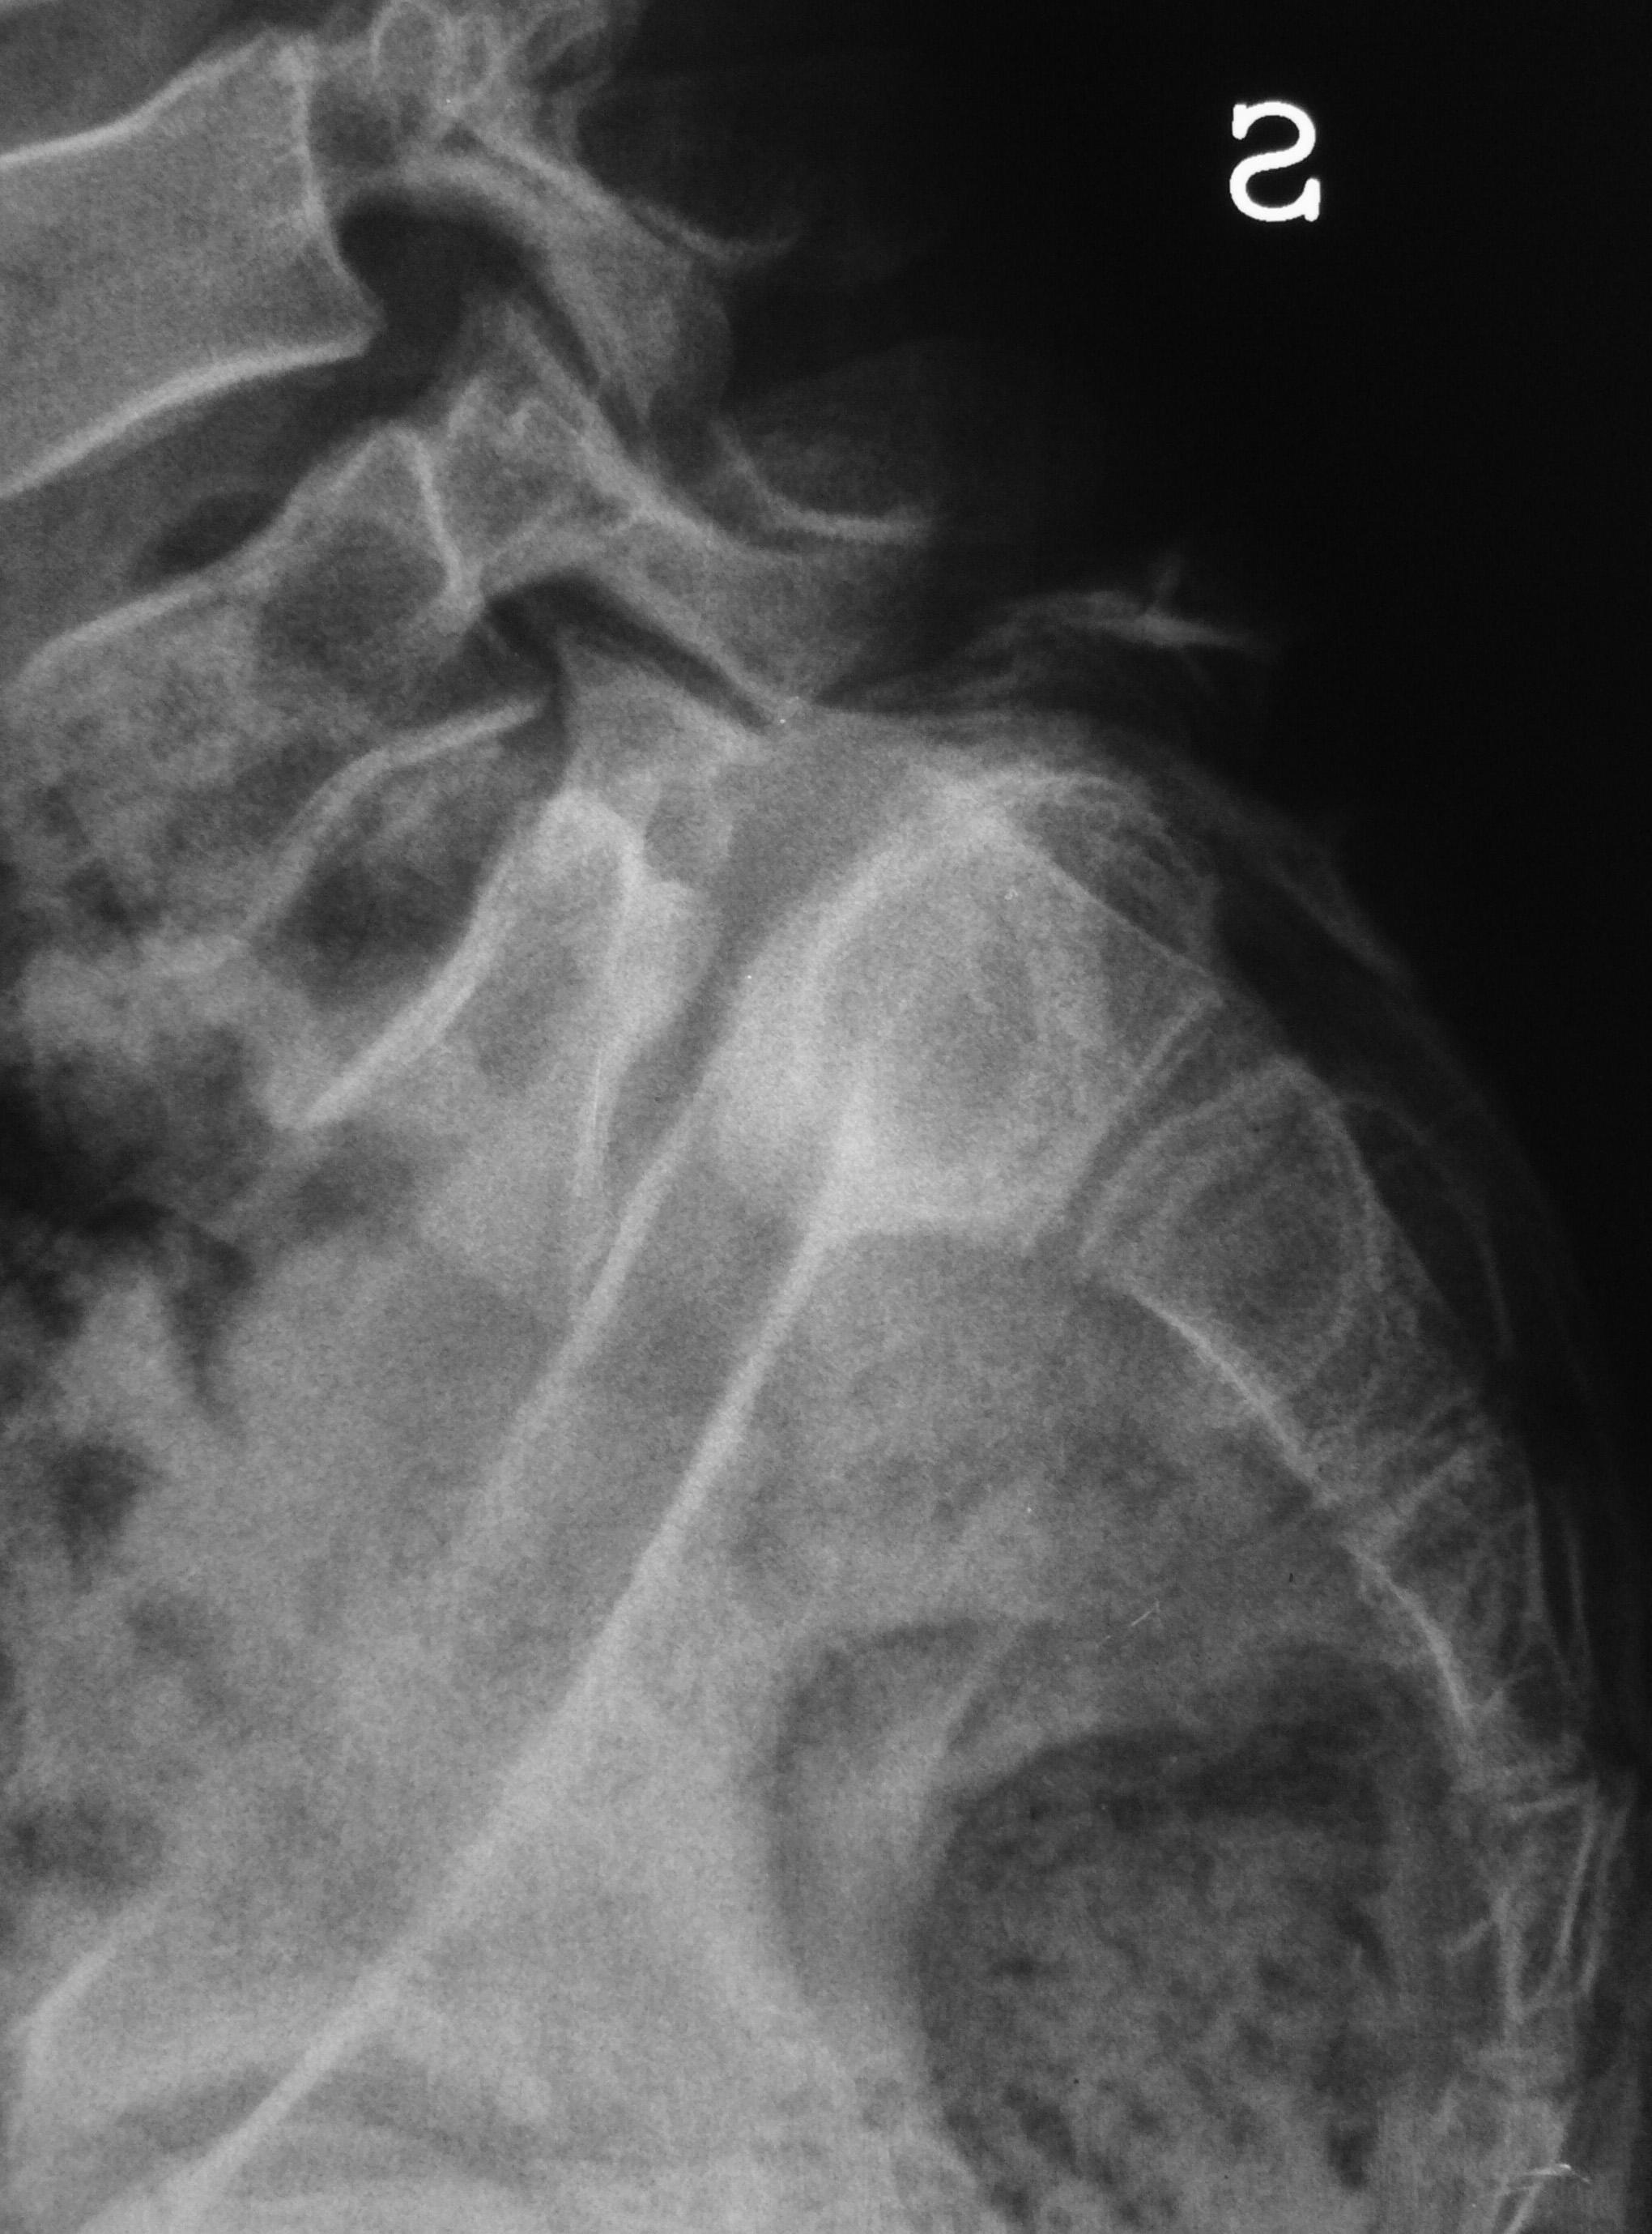

Il trattamento delle forme gravi di scoliosi idiopatica dell’adolescente, patologia più frequente nel sesso femminile, può richiedere un intervento chirurgico correttivo, che comprende una riduzione della deformità vertebrale, con apposizione di strumentario metallico, e la sua artrodesi, cioè la fusione dei metameri vertebrali interessati dalla curva. Il chirurgo vertebrale seleziona l’area da sottoporre ad intervento, per limitare una eccessiva rigidità a livello lombare, risparmiando il maggior numero di dischi intervertebrali caudali alla deformità (9,11). A volte, in presenza di gravi curve lombari, può essere però indispensabile estendere l’artrodesi a L4 o persino a L5. In questi casi è limitata la possibilità di flettere il tronco, e la forza del torchio addominale può essere diminuita (figura 3).

Occorre considerare inoltre come in un rachide sottoposto ad artrodesi vertebrale posteriore possa risultare impossibile l’accesso al canale vertebrale per l’esecuzione di una analgesia peridurale.